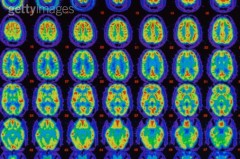

Μια νέα μέθοδο διάγνωσης της νόσου Αλτσχάιμερ ανέπτυξαν οι ειδικοί του Κέντρου Βιοϊατρικής Έρευνας Νοητικής Υγείας, του νοσοκομείου Maudsley και του King’s College του Λονδίνου. Οι Βρετανοί επιστήμονες ανέπτυξαν μια μέθοδο σάρωσης εγκεφάλου ικανή να εντοπίζει πρώιμα σημάδια της νευροεκφυλιστικής νόσου σε λιγότερο από 24 ώρες και με ακρίβεια που αγγίζει το 85%. Η νέα διαγνωστική μέθοδος χρησιμοποιεί αναλυτικές σαρώσεις του εγκεφάλου που προέρχονται από μαγνητική τομογραφία (MRI). Στη συνέχεια, ένα προηγμένο λογισμικό συγκρίνει τις εικόνες αυτές με μια βάση δεδομένων όπου υπάρχουν 1.200 τομογραφίες άλλων ασθενών – οι μισοί από τους οποίους έχουν διαγνωσθεί θετικοί στη νόσο. «Για την ώρα, η διάγνωση πρώιμου Αλτσχάιμερ είναι πολύ δύσκολη» αναφέρει ο Δρ Άντι Σίμονς, ένας εκ των ειδικών που βοήθησε στην ανάπτυξη του τεστ.